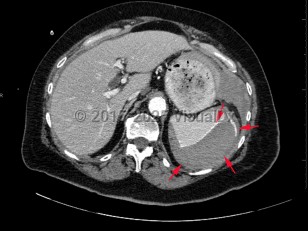

Imaging Studies image of Splenic rupture - imageId=7872924. Click to open in gallery.  caption: '<span>Axial CT image of the abdomen  demonstrates a large subcapsular splenic hematoma, with evidence of  active contrast extravasation and hemoperitoneum. Findings were  consistent with splenic rupture.</span>'

Axial CT image of the abdomen demonstrates a large subcapsular splenic hematoma, with evidence of active contrast extravasation and hemoperitoneum. Findings were consistent with splenic rupture.